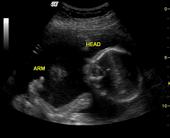

26776708